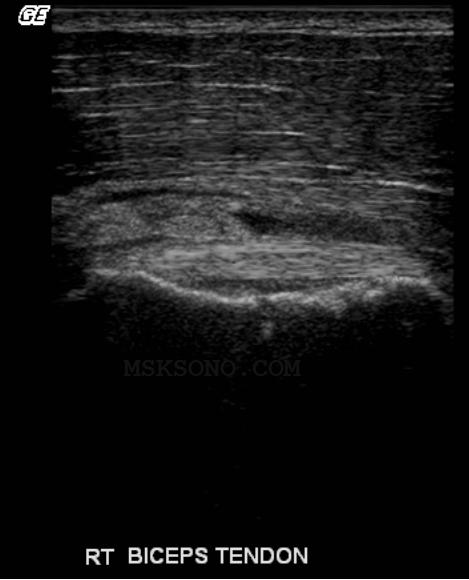

Bicep tendon

resting in the

footprint of the

Subscapularis

Tendon region

Scanning a little more

anterior shows a Bicep

Groove filled with

unorganized tissue.